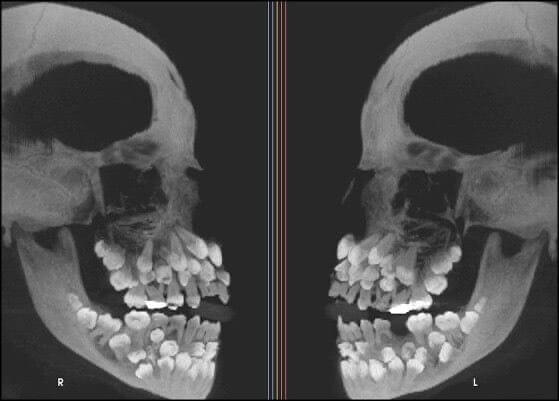

Why Toddlers Have Incredibly Terrifying X-Rays

Toddlers are adorable little humans, no doubt. We love them, at least when they are not screaming on a plane. At their best, they bring joy to strangers and make us hope for a better future. But here, we see an actual X-ray of a little one. Would you believe that they have all their adult teeth hidden under their eyes? We would have never guessed, and we're not sure we wanted to know.

If you think about it, it makes sense. We all lost our baby teeth and saw new ones appear in our mouths. Where could they have come from, except from inside our own heads? Well, here they are. You're welcome!